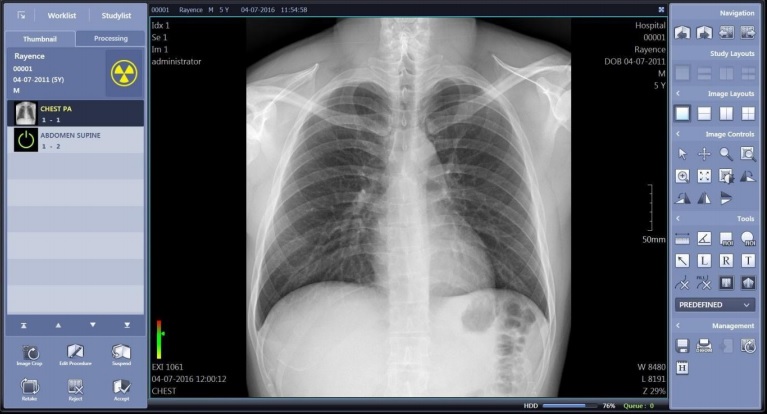

Безупречное качество рентгеновских снимков

Компания RAYENCE — производитель плоскопанельных детекторов с мировым именем. Детальная проработка элементов и многоуровневые испытания позволили добиться высочайшего качества изображений. Цифровой плоскопанельный детектор RAYENCE обеспечивает удобство в работе специалистов, обладает повышенной прочностью. Просмотреть полученное изображение можно на экране консоли уже через 2 секунды после экспозиции.

Программное обеспечение XmaruView V позволяет управлять информацией о пациентах, исследованиями и изображениями с использованием внутренней базы данных. Поддерживает протокол DICOM, который обеспечивает отличную совместимость с другим рентгенологическим оборудованием и сетевыми программами.